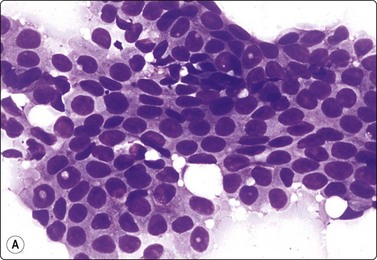

A comparison between the basic benign pattern (non-neoplastic glandular tissue) and the most common malignant pattern (low-grade carcinoma of no special type) in FNB of breast lesions is given in Table 7.2 (Figs 7.2-7.4).

Table 7.2 Comparison of the benign pattern and low-grade carcinoma in FNB smears

Non-neoplastic breast tissue (Figs 7.2A, 7.3A and 7.4A) Low-grade carcinoma NOS (Figs 7.2B, 7.3B and 7.4B)

1. Overall low cell yield 1. Variable but higher cell yield

2. Sheets and aggregates of cohesive, small, uniform cells 2. Irregular clusters of less cohesive, small, mildly irregular cells

3. Small rounded nuclei, bland chromatin, some overlapping 3. Slightly larger and darker nuclei, relatively bland chromatin

4. Myoepithelial cell nuclei among epithelial cells 4. Myoepithelial cell nuclei not seen

5. Variable numbers of single, bare, bipolar nuclei scattered in the background 5. Single cells, most with some cytoplasm, identical to those forming clusters; no bare bipolar nuclei

image image

Fig. 7.2 Non-neoplastic glandular breast tissue and low-grade duct carcinoma

Low-power view; (A) Bimodal population of epithelial sheets and single bipolar nuclei of non-neoplastic glandular breast tissue; (B) Single population of epithelial cells in low-grade carcinoma (MGG, LP).

Fig. 7.3 Non-neoplastic glandular breast tissue and low-grade duct carcinoma

High-power view, air-dried smears; (A) Non-neoplastic glandular breast tissue; (B) Low-grade duct carcinoma. Note single bipolar nuclei in A, and absence of bipolar nuclei, relatively mild nuclear atypia and some loss of cohesion of malignant cells in B (MGG, HP).

Fig. 7.4 Non-neoplastic glandular breast tissue and low-grade duct carcinoma

High-power view, Pap-stained smears; (A) Bimodal population in smear from non-neoplastic breast; (B) Single and clustered cells in low-grade carcinoma; some single cells probably stromal (Pap, HP).

The basic benign pattern is common to normal glandular breast tissue. Variations occur with the menstrual cycle and with the age of the patient, depending upon the variable proportions between epithelial cells and fibrous stroma. The yield of the needle biopsy is usually scanty and multiple biopsies should always be made to increase the likelihood that the material is representative.

The bimodal pattern of cohesive groups of epithelial cells and scattered single, bare, oval/bipolar nuclei is diagnostic of benign, non-neoplastic breast tissue. Ductular epithelial cells – this term is used here to designate cells from the intralobular epithelial structures of the resting breast, which differ distinctly from the acinar epithelial cells seen in pregnancy and lactation (see below) – are cohesive and are seen as small epithelial groups, which represent terminal ductules. The cohesiveness of non-neoplastic epithelium is in contrast to the dyscohesion of malignant cells unless very well differentiated (Figs 7.3 and 7.5). The nuclei are irregularly distributed within the groups and may appear crowded and overlapping (multilayered). They are uniform, small, round or oval, dark, with a granular chromatin. Nucleoli are indistinct or are very small. Cytoplasm is scanty, visible, but without distinct cell borders; it is pale and may show a blue granulation (MGG). Epithelial fragments from larger ducts are sometimes present. They form monolayered sheets of regularly arranged, slightly larger cells with uniform nuclei. The single, bare nuclei scattered in the background are of the same size or a little smaller than those of the epithelial cells. They have a bipolar/oval shape and a very smooth nuclear outline. The chromatin is dense and homogeneous and nucleoli are not seen (Figs 7.3A and 7.4A). The bipolar/oval nuclei sometimes wash off in heavily bloodstained and in wet-fixed smears. Nuclei of similar appearance can also be seen scattered between the cells of the epithelial fragments, distinguishable from these by their smaller size, bipolar shape, and darker staining (Fig. 7.6). They no doubt represent myoepithelial cells, whereas the single nuclei scattered in the background may be either myoepithelial or derived from the specialized, intralobular connective tissue. The number of bipolar/oval nuclei in smears corresponds closely to the cellularity of the lobular stromal component in sections. This is particularly evident in smears from fibroadenoma. However, a recent study of p63 immunoexpression in these cells concluded that the majority was of myoepithelial origin.91 Small fragments of collagen may be seen, particularly if larger-caliber needles have been used, but are usually inconspicuous, whereas fragments of adipose tissue are frequently present.